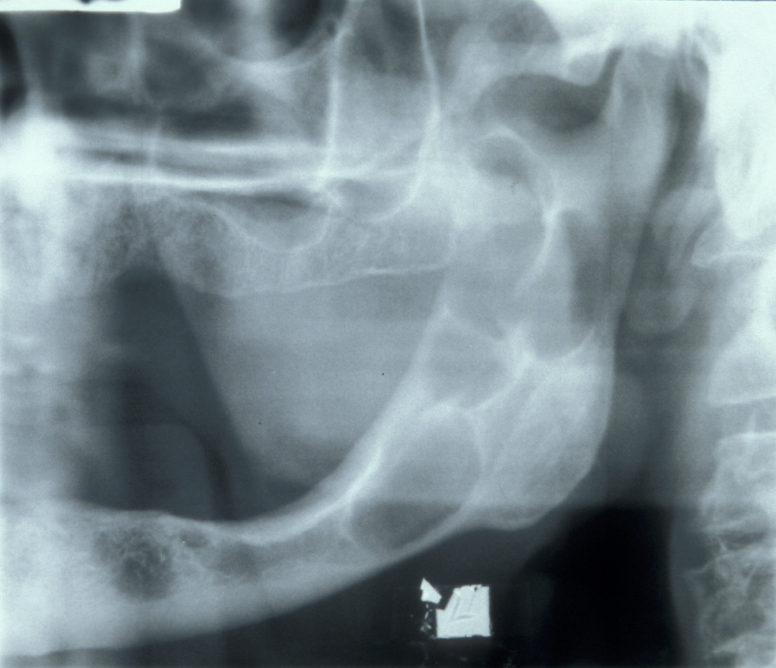

Clinically, solitary bone cysts are usually asymptomatic but there is occasionally bone expansion and radiographically there is an irregular radiolucency with well-defined scalloping between the roots of the teeth. Histological examination shows a thin layer of loose vascular fibrous tissue but no epithelial lining and there is no cyst fluid.